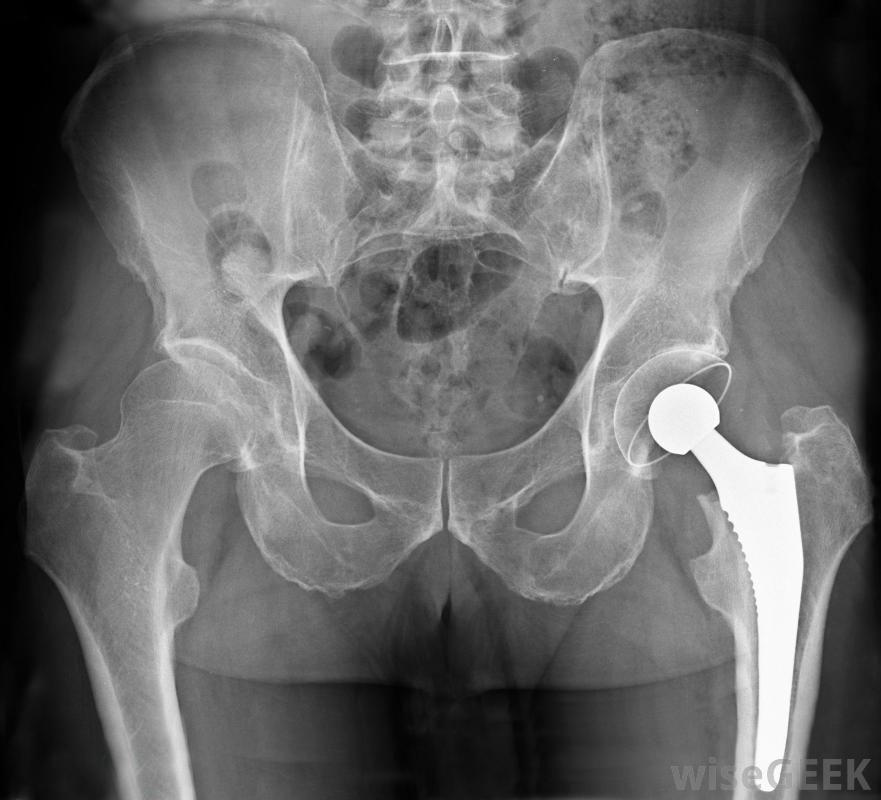

前路髖關節置換術的優缺點是什么(Pros and Cons of an Anterior Approach Hip Replacement)?

前路人工髖關節置換術是傳統髖關節置換術的一種替代方法,其優點是切口小,住院時間短,康復時間短,但有些病人很難找到合格的外科醫生,他們可能需要不止一次手術。前路髖關節置換術可以縮短康復時間外科醫生在髖關節前面開一個小切口進行前入路髖關節置換術。髖關節是在肌肉和肌腱之間進行的。手術過程中使用特殊的器械和特殊的手術臺來幫助外科醫生放置腿和髖關節,并允許他們在限制髖關節的同時進入髖關節肌肉和肌腱損傷。骨盆區域的X光片,顯示髖關節置換術采用這種方法,患者住院時間通常較短,康復時間也較短。在傳統的髖關節置換手術中,肌肉和肌腱被切斷,以便從髖關節外側進入并替換髖關節。這可能導致住院時間更長,以恢復從手術中然而,在前入路髖關節置換術中,參與髖關節功能的肌肉是單獨存在的,這意味著患者在手術后立即可以在髖關節處正常彎曲。在其他類型的髖關節置換手術中,在恢復期,髖關節的運動和活動范圍有許多限制接受前路髖關節置換術的患者可能需要物理治療前路入路,脫位的風險較低,準確控制腿部長度的能力更強,這在很大程度上是由于患者在手術過程中仰臥而不是側臥髖關節置換術后可能發生脫位。找到一名外科醫生進行前入路髖關節置換術可能很困難。這種手術在世界上一些地方仍然是比較新和不常見的特殊的訓練和設備是進行手術所必需的,許多習慣了傳統手術的外科醫生會堅持他們所知道的。病人可能需要走這么遠才能找到使用這種方法的外科醫生手術有一些缺點,包括病人需要翻修手術的風險它還可能導致感染、周圍神經損傷和骨折。與所有髖關節置換手術一樣,髖關節脫位也是可能的,雖然這種手術的風險較小。前路髖關節置換術的優點包括切口小、住院時間縮短、康復時間縮短。